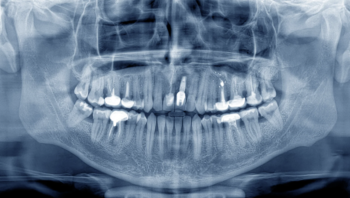

インプラント治療では、**CT撮影による三次元的な診断**が欠かせません。

CT画像を使うことで、顎の骨の量や質、神経や血管の位置を正確に把握でき、安全な手術計画を立てることができます。

さらに、3Dシミュレーションソフトを使って、インプラントを埋め込む位置や角度、深さを事前に決定します。これにより、見た目と噛み合わせのバランスを考慮した「最適な位置」にインプラントを配置できます。

CT撮影を行い、顎の骨の量や質、神経や血管の位置を3次元的に確認します。

当院では、このCT画像をもとに3Dシミュレーションを実施し、見た目と噛み合わせのバランスを踏まえた「一番良い位置」を計画します。骨が足りない場合には、骨を増やす処置(骨造成)も含めて検討し、必要に応じてガイデッドサージェリーという精密な手術方法を選択します。